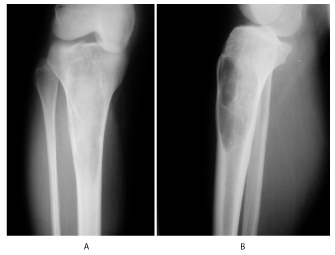

A 33 year - old female patient presented for right leg pain of a five week duration, exacerbated by weight bearing without disappearing at rest or at night. She estimates the pain as 6 over 10, relieved with non-steroidal anti - inflammatory agents. She is previously healthy without any history of trauma. There is mild edema, no redness, and mild increase of the pain upon palpation. There are no neurovascular abnormalities. Examination of the back, hip, and knee is normal. X-ray showed a large hypolucent spherical lesion in the proximal third of the tibia (Figure 1). MRI on T1 showed the lesion to be hypointense, and on T2 to be hyperintense (Figure 2,3). The lesion showed to be osteolytic, extending anteroposteriorly through the cortex at some levels, but it did not reach the articular surface, nor the surrounding soft tissues. Decision was taken to biopsy it. The pathology report showed lamellated cysts and scattered scoleces. Albendazole 400 mg was given orally twice per day for 2 months. Extensive curettage was done through excision of bone layers with a burr, then phenolization and grafting of cancellous bone chips inside the cavity. The patient was free clinically and radiologically of the disease for two years, then in the third year, multilocular cysts reappeared on x-ray (Figure 4), with possible extension to the articular surface. A decision of total knee arthroplasty was taken after wide resection of the diseased segment (Figure 5). Negative margins were obtained. The patient post operatively was rehabilitated; pain subsided with no radiological signs of recurrence. She was given albendazole 400 mg orally twice per day for 3 months.